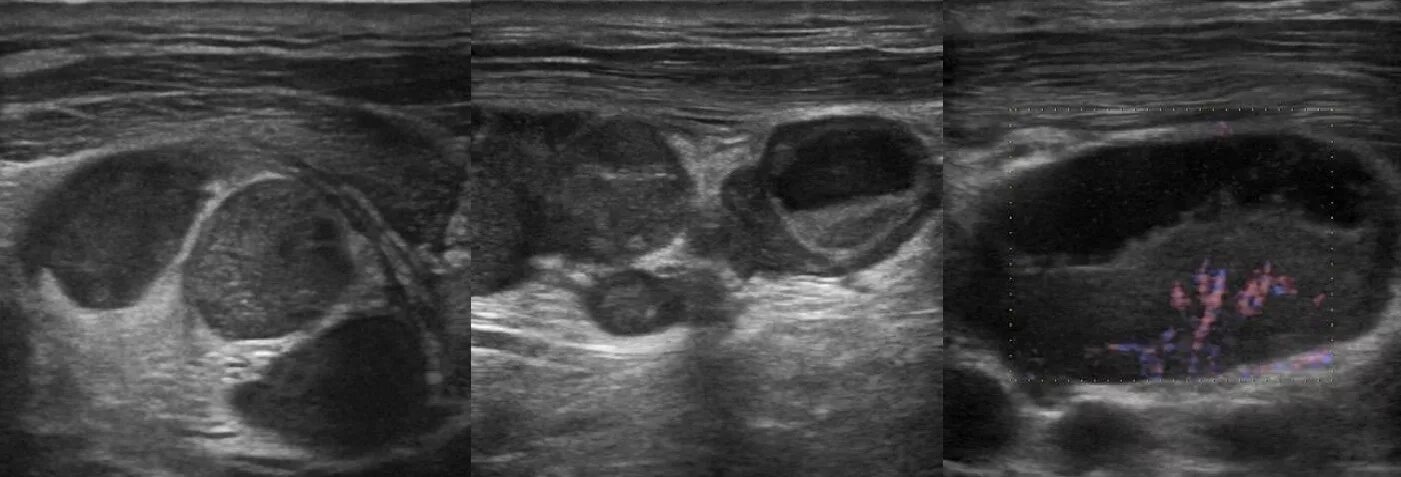

Метастазы в паховых лимфоузлах